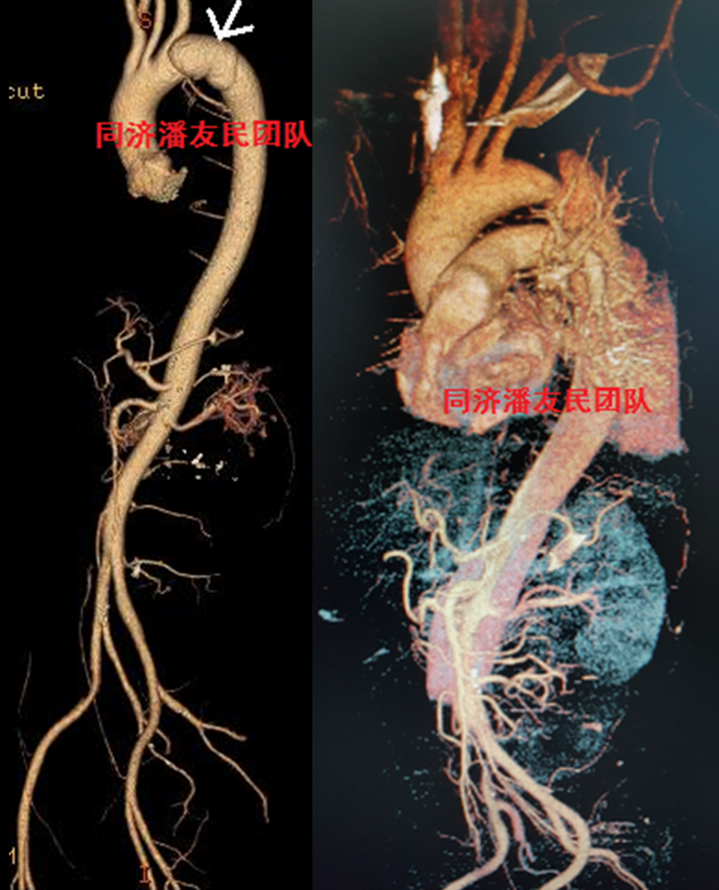

外伤性主动脉夹层进行腔内治疗,腹部外伤情况也进行了相应处理。患者出院前复查CTA,情况良好(图5)。

图5:腔内治疗术后复查情况良好

图11 左图显示外伤性主动脉夹层,局限性(红箭头所示),右图显示腔内治疗后情况良好。